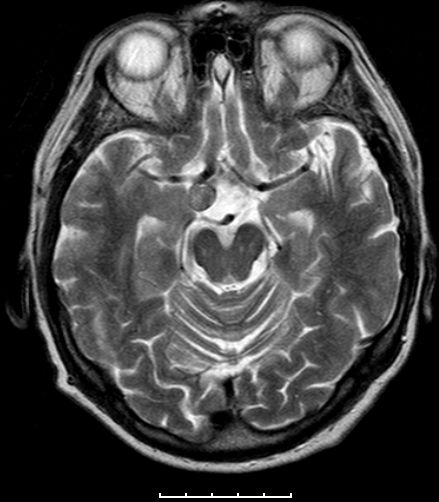

| Adenom | 78jährige Frau. Hypophysenadenom

seit 2 Jahren bekannt. Jetzt Deviation des rechten Auges und Kopfschmerzen.![]() |

![]() Das Adenom ist in die Keilbeinhöhle eingewachsen. |

![]() Infraselläre Ausbreitung mit Ummauerung der Arteria carotis interna rechts. | ||||||||||||||||||||||||||